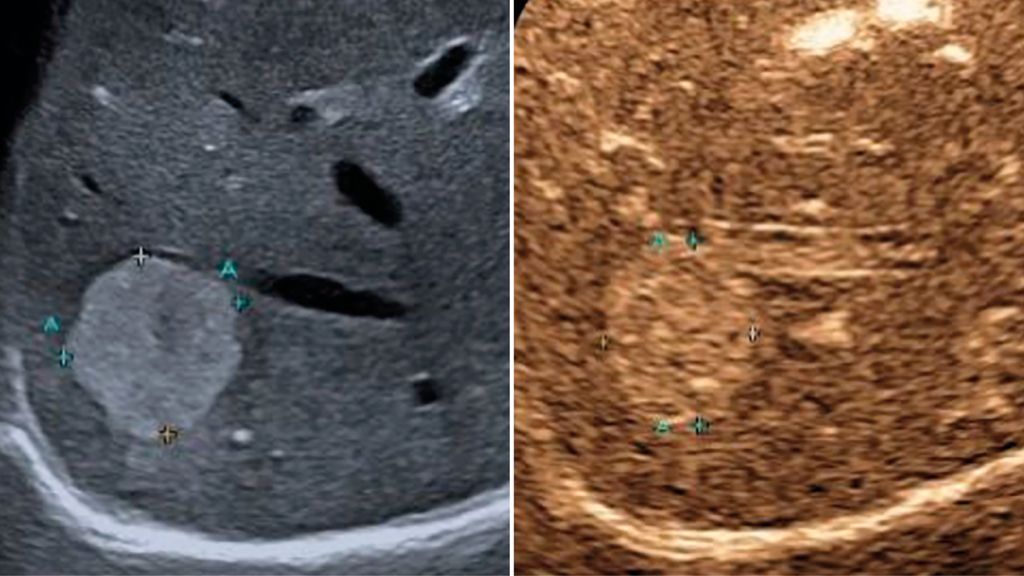

In der früharteriellen Phase zeigen benigne Läsionen wie Hämangiome typische Füllungsmuster ohne „wash-out“ in der Portal- oder Spätphase (Abb.1). Maligne Läsionen hingegen weisen meist ein rasches „wash-out“ auf und stellen sich in der Spätphase hypokontrastiert dar (Abb.2).3,4

Abb. 1: Typisches Kontrastmittelverhalten eines Hämangioms in der Spätphase mit Hyperenhancement gegenüber dem umgebenden Leberparenchym (rechts)

Abb. 2: Darstellung einer hochgradig Metastasen-suspekten Raumforderung bei Mamma-Neoplasie im linken Leberlappen im B-Bild-Modus (rechts) sowie in der Spätphase nach Gabe von 1,6 ml SonoVue® mit Darstellung eines deutlichen „Wash-out“-Phänomens in der Spätphase 4 Minuten nach Injektion des Kontrastmittels (links)